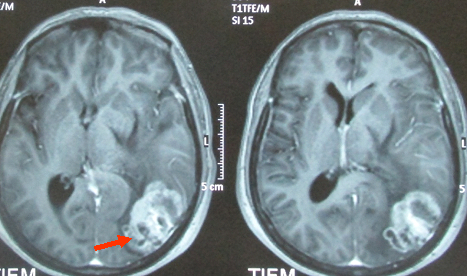

• MRI sọ não cho thấy khối u vùng chẩm trái kích thước (3,5x5)cm ngấm thuốc sau tiêm, có phù não xung quanh (hình 2).

Hình 2: Hình ảnh chụp MRI sọ não cho thấy khối u vùng chẩm trái, kích thước (3,5x5)cm ngấm thuốc sau tiêm,có phù não xung quanh.

Hình 4: Hình ảnh chụp MRI sọ não sau 6 tháng cho thấy sau hóa chất Navelbine và xạ trị toàn não u não thu nhỏ nhiều, kích thước còn (1,8x2,5)cm.